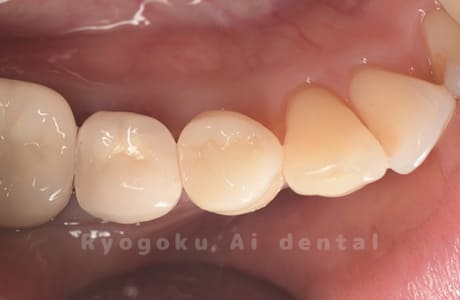

Case02

-

- 原因

- 縁下カリエス、慢性根尖性歯周炎、不良補綴

- 治療期間

- 約6ヶ月

- 治療内容

- クラウンレングスニング、マイクロエンド、フルジルコニアクラウン

- 治療費用

- 約840,000円

虫歯が神経まで及ぶと共に、歯茎の中まで虫歯が及んでいました。根の治療(マイクロエンド・根管治療)を行なった後、クラウンレングスニング・歯周外科を行い、ジルコニアの被せ物を行った患者様です。

<リスク・副作用>

過度の咬合や衝撃で割れることがあります。